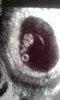

Ehkä nyt uskaltaa hetken huokasta helpotuksesta ja alkaa nauttimaan tästä raskaudesta pahoinvoinnin kera